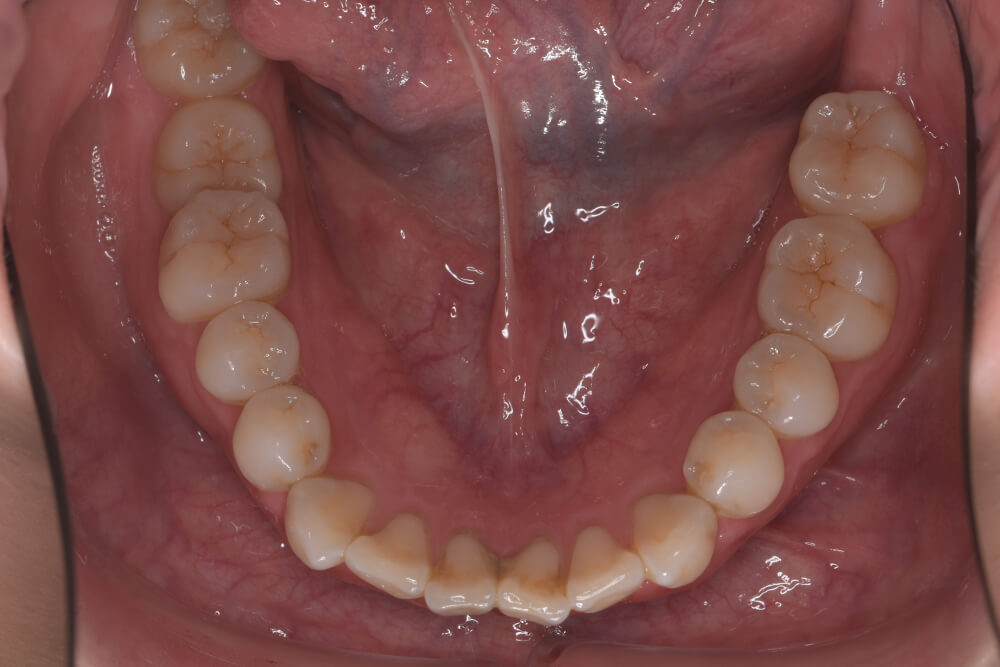

CASE07

Before

After

| コース | 7回コース |

|---|---|

| IPR | 1回 |

| 治療期間 | 8ヶ月 |

| 治療費 | 256,300円 |

| 年齢・性別 | 30代女性 |